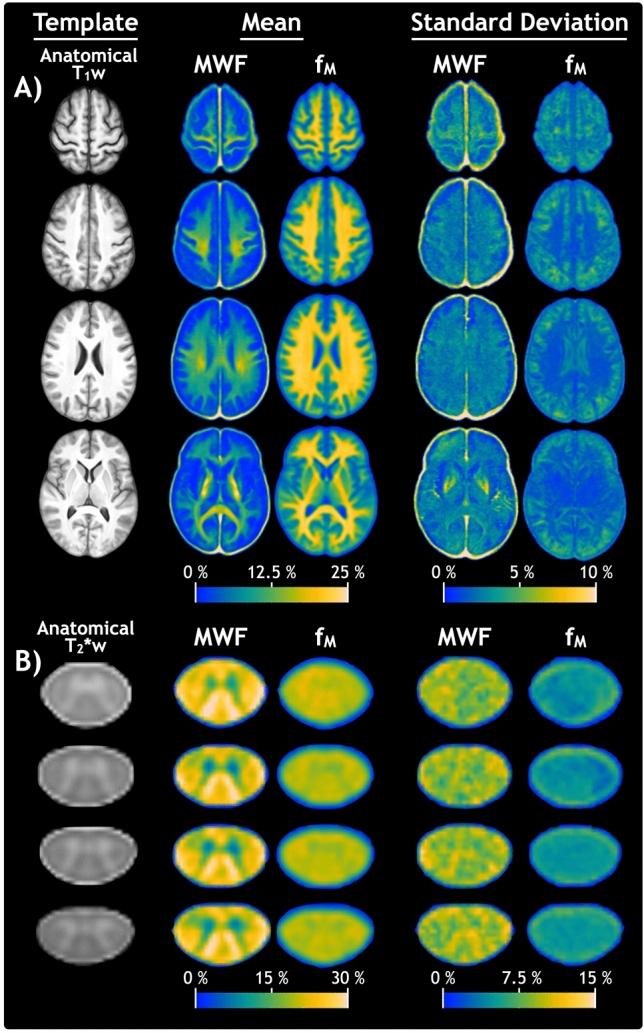

The traditional approach for measuring myelin-associated water with quantitative magnetic resonance imaging (MRI) uses multi-echo T relaxation data to calculate the myelin water fraction (MWF). A fundamentally different approach, abbreviated "mcDESPOT", uses a more efficient steady-state acquisition to generate an equivalent metric (f). Although previous studies have demonstrated inherent instability and bias in the complex mcDESPOT analysis procedure, f has often been used as a surrogate for MWF. We produced and compared multivariate atlases of MWF and f in healthy human brain and cervical spinal cord (available online) and compared their ability to detect multiple sclerosis pathology. A significant bias was found in all regions (p < 10), albeit reversed for spinal cord (f-MWF =  - 3.4%) compared to brain (+ 6.2%). MWF and f followed an approximately linear relationship for regions with MWF <  ~ 10%. For MWF >  ~ 10%, the relationship broke down and f no longer increased in tandem with MWF. For multiple sclerosis patients, MWF and f Z score maps showed overlapping areas of low Z score and similar trends between patients and brain regions, although those of f generally had greater spatial extent and magnitude of severity. These results will guide future choice of myelin-sensitive quantitative MRI and improve interpretation of studies using either myelin imaging approach.

传统的使用定量磁共振成像(MRI)测量髓鞘相关水的方法是使用多回波 T 弛豫数据来计算髓鞘水分数(MWF)。一种简写为“mcDESPOT”的方法则采用了更有效的稳态采集来生成等效指标(f)。尽管先前的研究已经证明了复杂的 mcDESPOT 分析过程中存在固有不稳定性和偏差,但 f 经常被用作 MWF 的替代物。我们制作并比较了健康人脑和颈脊髓的 MWF 和 f 的多变量图谱(可在线获取),并比较了它们检测多发性硬化病变的能力。在所有区域都发现了显著的偏差(p<10),尽管与大脑(+6.2%)相比,脊髓(f-MWF= -3.4%)的偏差相反。MWF 和 f 对于 MWF<10%的区域呈近似线性关系。对于 MWF>10%,关系破裂,f 不再与 MWF 同步增加。对于多发性硬化症患者,MWF 和 f Z 分数图显示了低 Z 分数的重叠区域,以及患者和大脑区域之间的相似趋势,尽管 f 的区域通常具有更大的空间范围和严重程度。这些结果将指导未来选择髓鞘敏感的定量 MRI,并改善使用任何髓鞘成像方法的研究的解释。